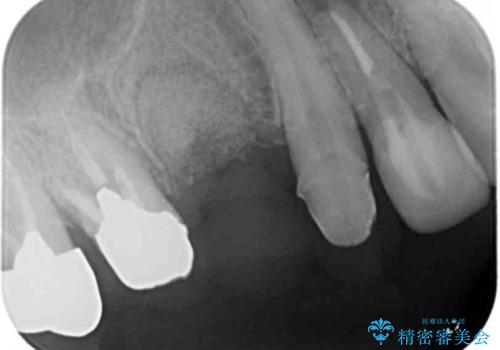

- ぐらぐらする小臼歯の治療を求めて来院されました。

X線検査、歯周組織検査より、歯は割れてしまい周囲の骨が高度に吸収してしまっている状態でした。

合わせて周囲の根尖病変や銀歯を治療するためにインプラントではなく、ご相談の上ブリッジ治療を行う治療計画としました。